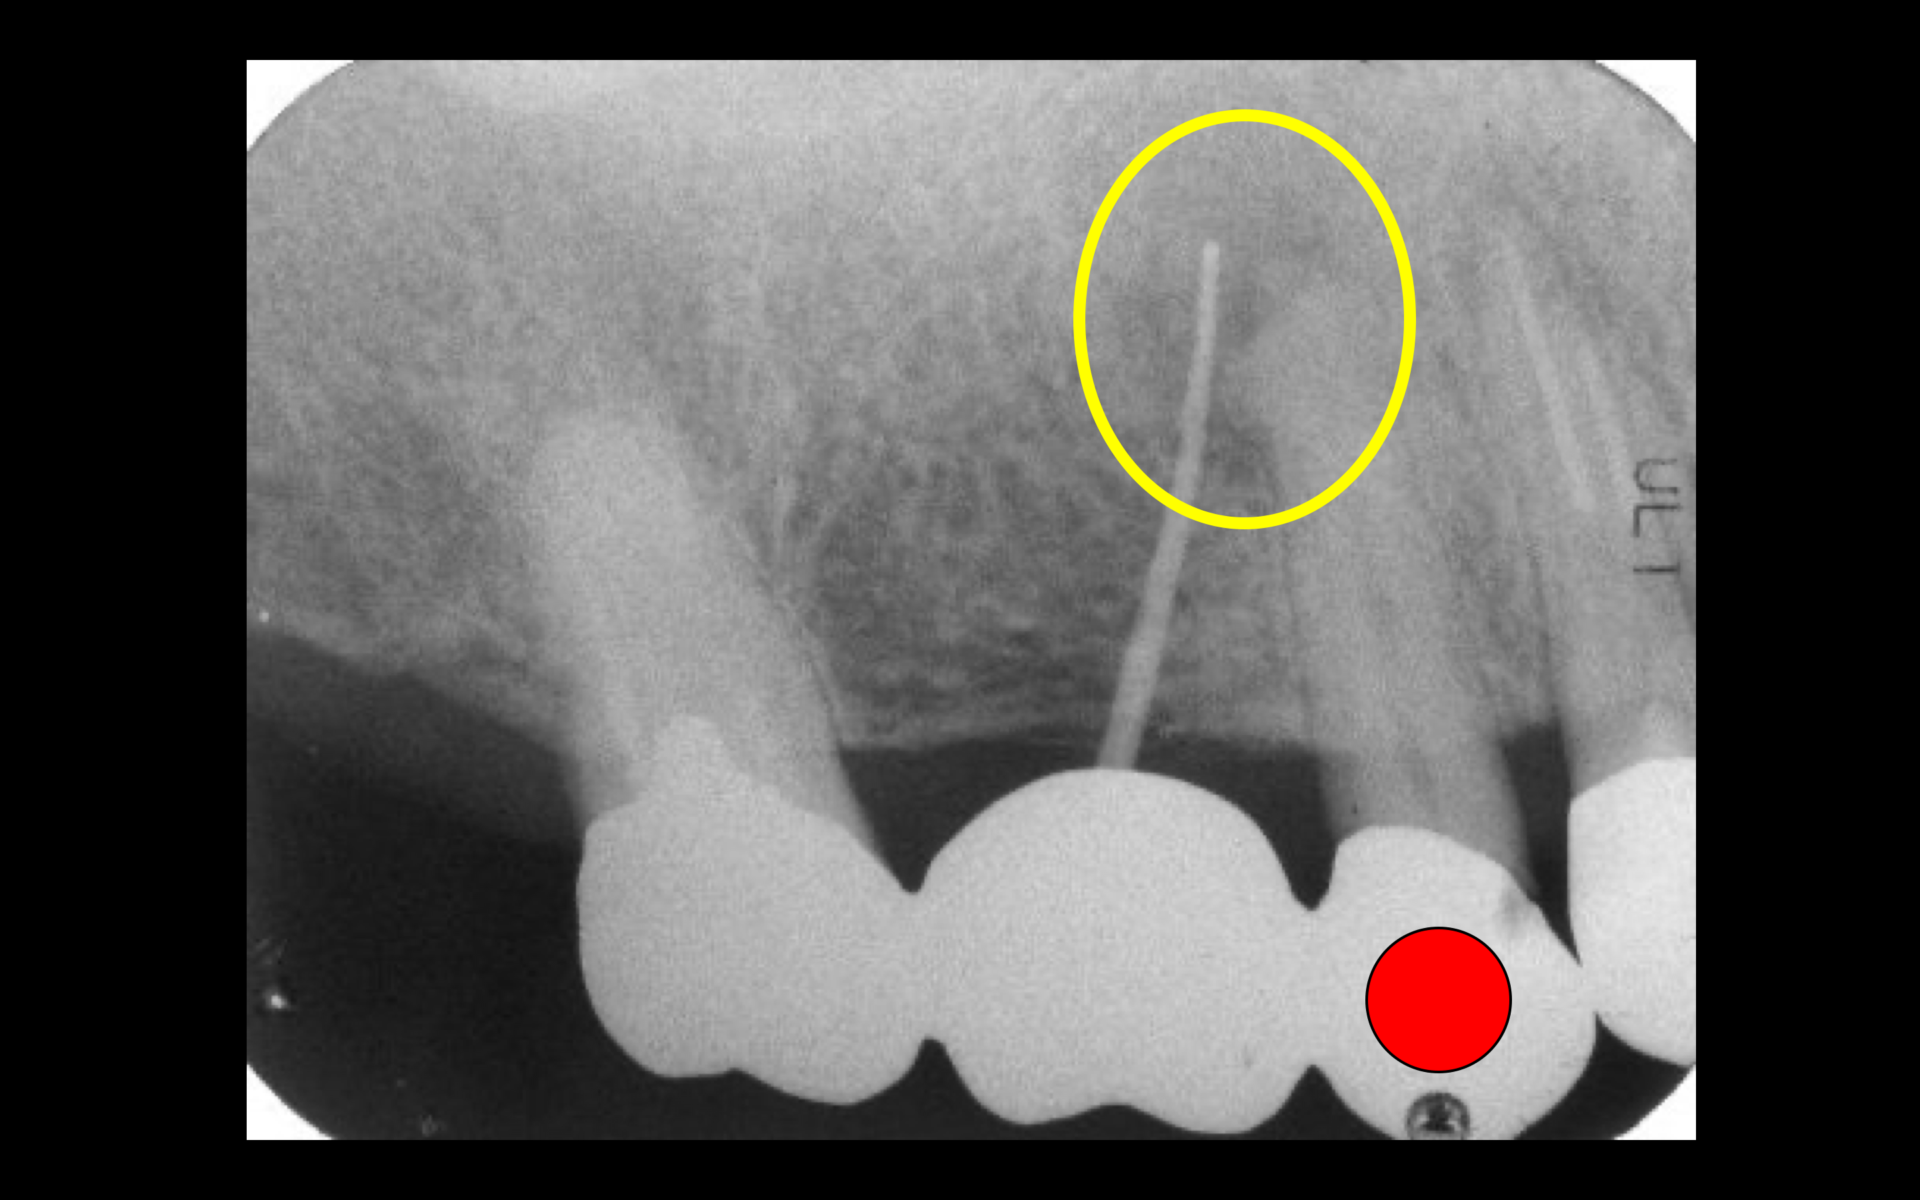

レントゲン所見より、黄色の円の中にある黒い部分が病変である。歯肉の腫れている原因は赤い点で記している上顎第二小臼歯の根尖病変であることが分かったため、精密根管治療を行うことになった。

精密根管治療1年後のレントゲン。主訴であった赤い点で記した第二小臼歯の根尖病変は消失し、骨が再生された(黄色の円の部分)